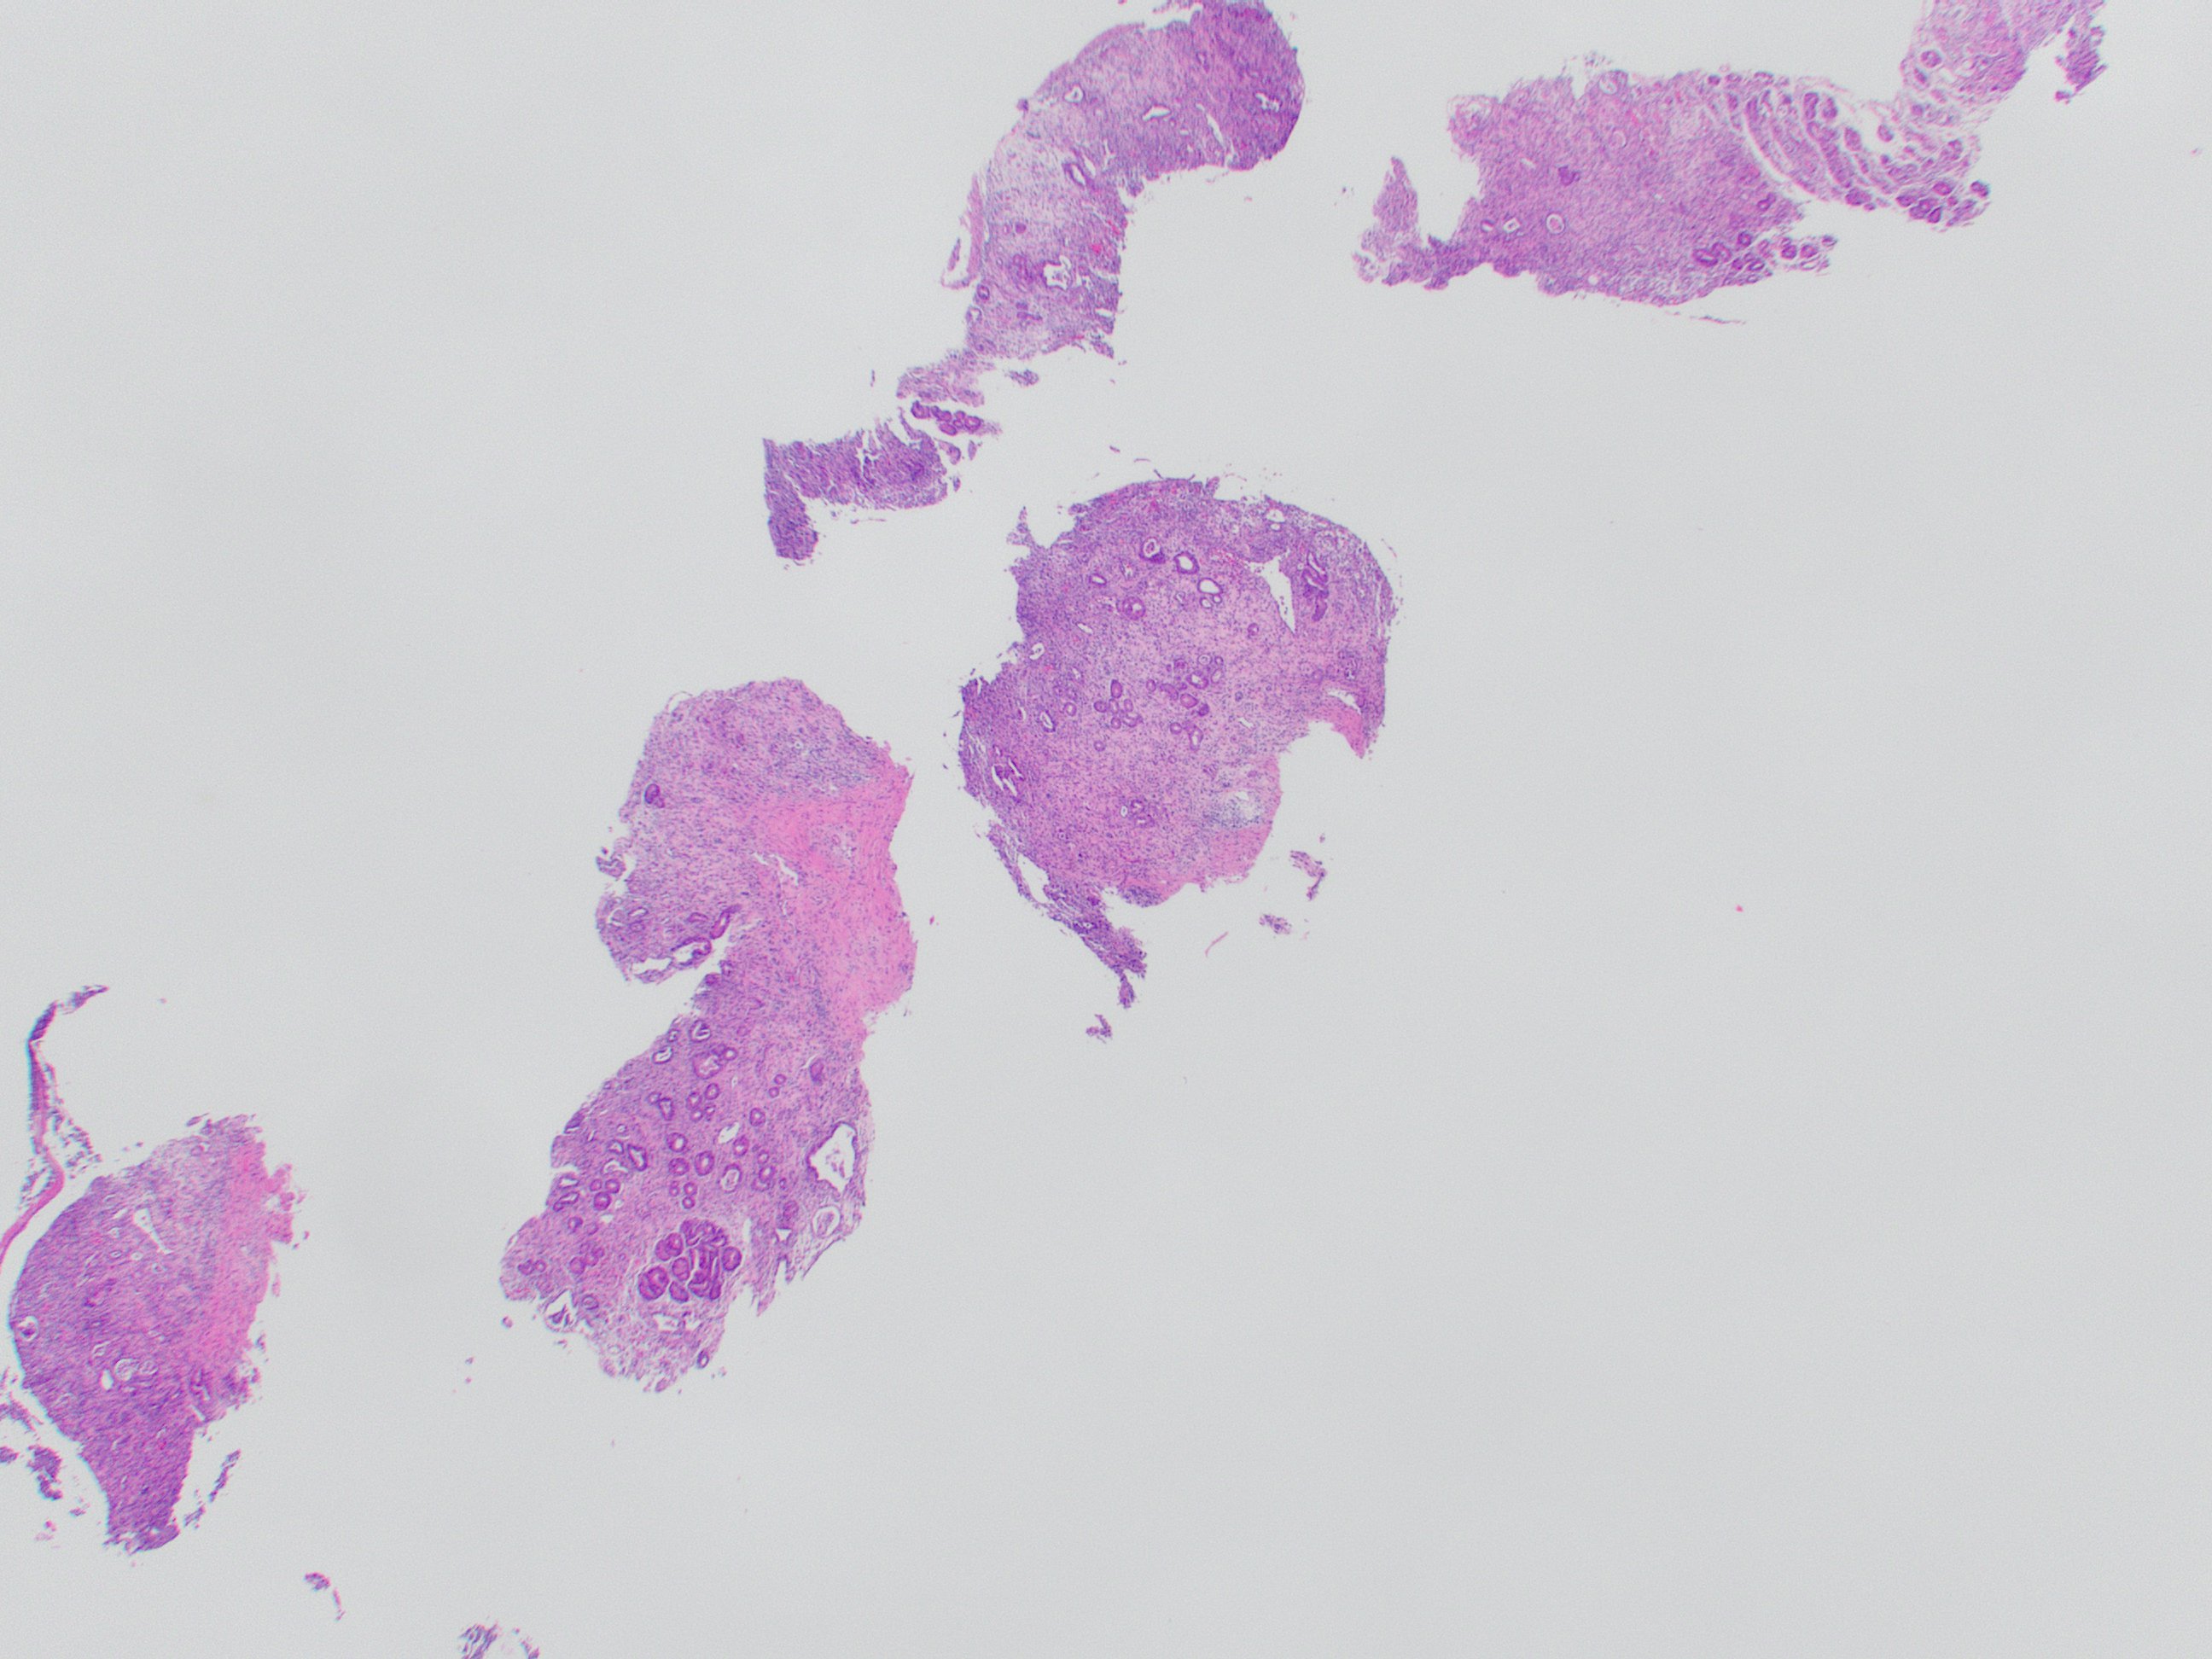

That covers the basics! Here is a direct side-by-side before and after editing in GIMP:

That covers the basics! Here is a direct side-by-side before and after editing in GIMP: